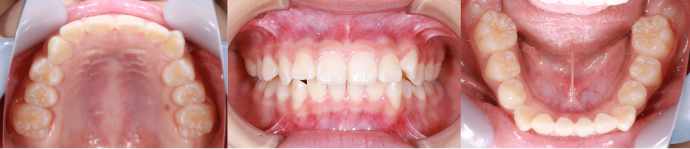

| Case3 |

| 受け口 |

| <治療前> |

|

| <治療後> |

| 主訴 |

上の歯がねじれている |

| 診断名 |

叢生を伴う反対咬合 |

| 年齢 |

10歳 |

| 使用装置 |

マルチブラケット装置 |

| 抜歯部位 |

永久歯の抜歯は無し |

| 治療期間 |

3年6か月 |

| 治療費概算 |

検査・診断料:5万円+税 装置・技術料:25万円+税 おおよそ1か月ごとの処置・管理料:5,000円+税 保定装置料:5万円+税 |

| リスク・副作用 |

う蝕 |